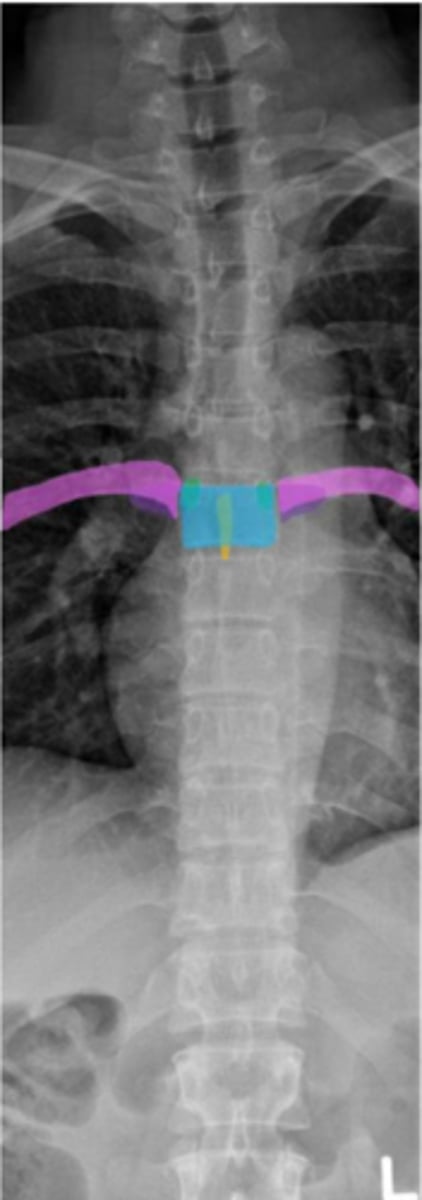

thoracic

What vertebrae is being examined?

thoracic vertebral body

Identify the blue structure

spinous process

Identify the yellow structure

pedicles

Identify the green structure

transverse processes

Identify the purple structure

rib

Identify the pink structure